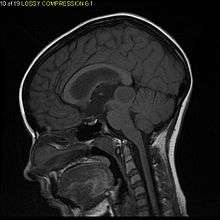

Pilocytic astrocytoma or juvenile pilocytic astrocytoma or cystic cerebellar astrocytoma (and its variant juvenile pilomyxoid astrocytoma) is a brain tumor that occurs more often in children and young adults (in the first 20 years of life). They usually arise in the cerebellum, near the brainstem, in the hypothalamic region, or the optic chiasm, but they may occur in any area where astrocytes are present, including the cerebral hemispheres and the spinal cord. These tumors are usually slow growing and benign.[1] The neoplasms are associated with the formation of a single (or multiple) cyst(s), and can become very large.

Pilocytic astrocytomas are often cystic, and, if solid, tend to be well-circumscribed. It is characteristically easily seen on CT scans and MRI.

Usually—depending on the interview of the patient and after a clinical exam which includes a neurological exam, and an ophthalmological exam—a CT scan and or MRI scan will be performed. A special dye may be injected into a vein before these scans to provide contrast and make tumors easier to identify. The neoplasm will be clearly visible.